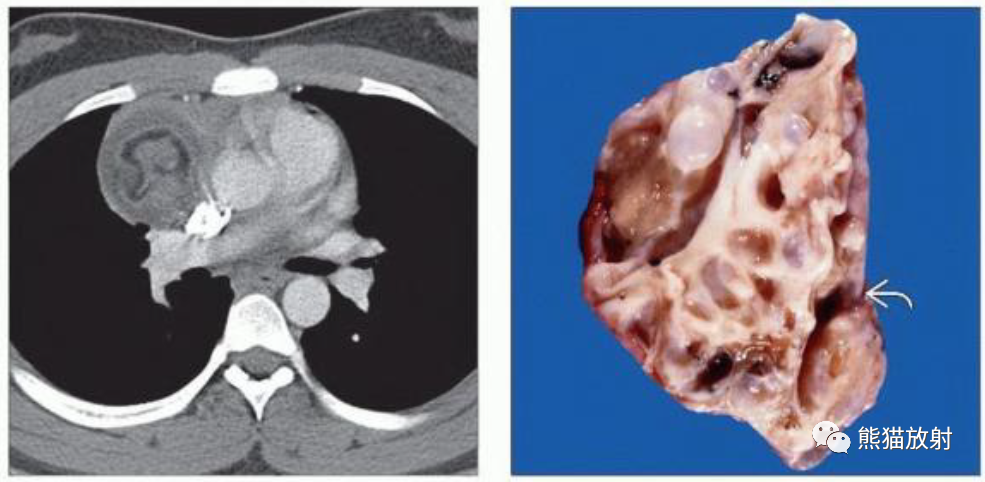

(左)16岁男孩,成熟囊性畸胎瘤,轴位CECT显示右前纵隔肿块,具有软组织、液体和脂肪密度成分。成熟畸胎瘤通常是囊性的,75%可见脂肪密度。

(右)成熟性畸胎瘤的切片显示多个囊性区域(弯箭)与实性软组织成分混合。肿瘤的不均质性导致CT上的特征性表现。